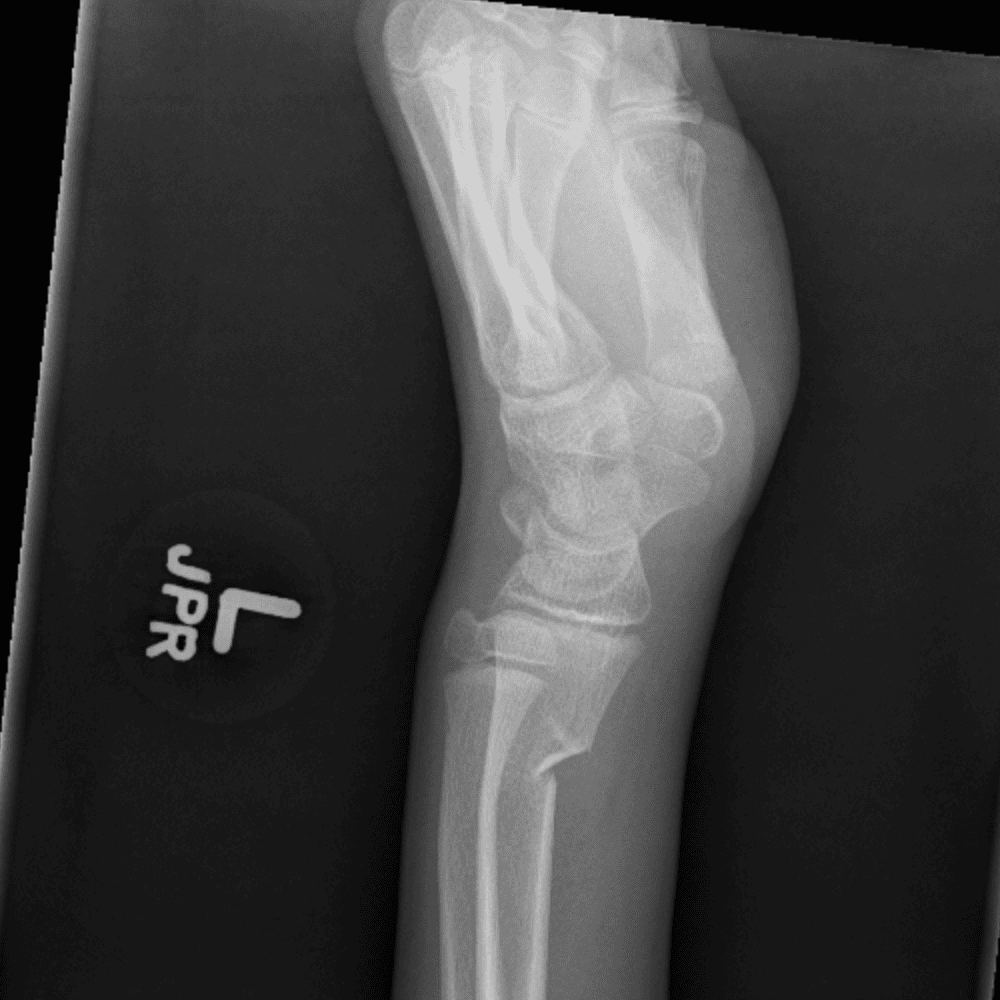

Simulates call by including subtle or difficult cases and some normals.

30 cases